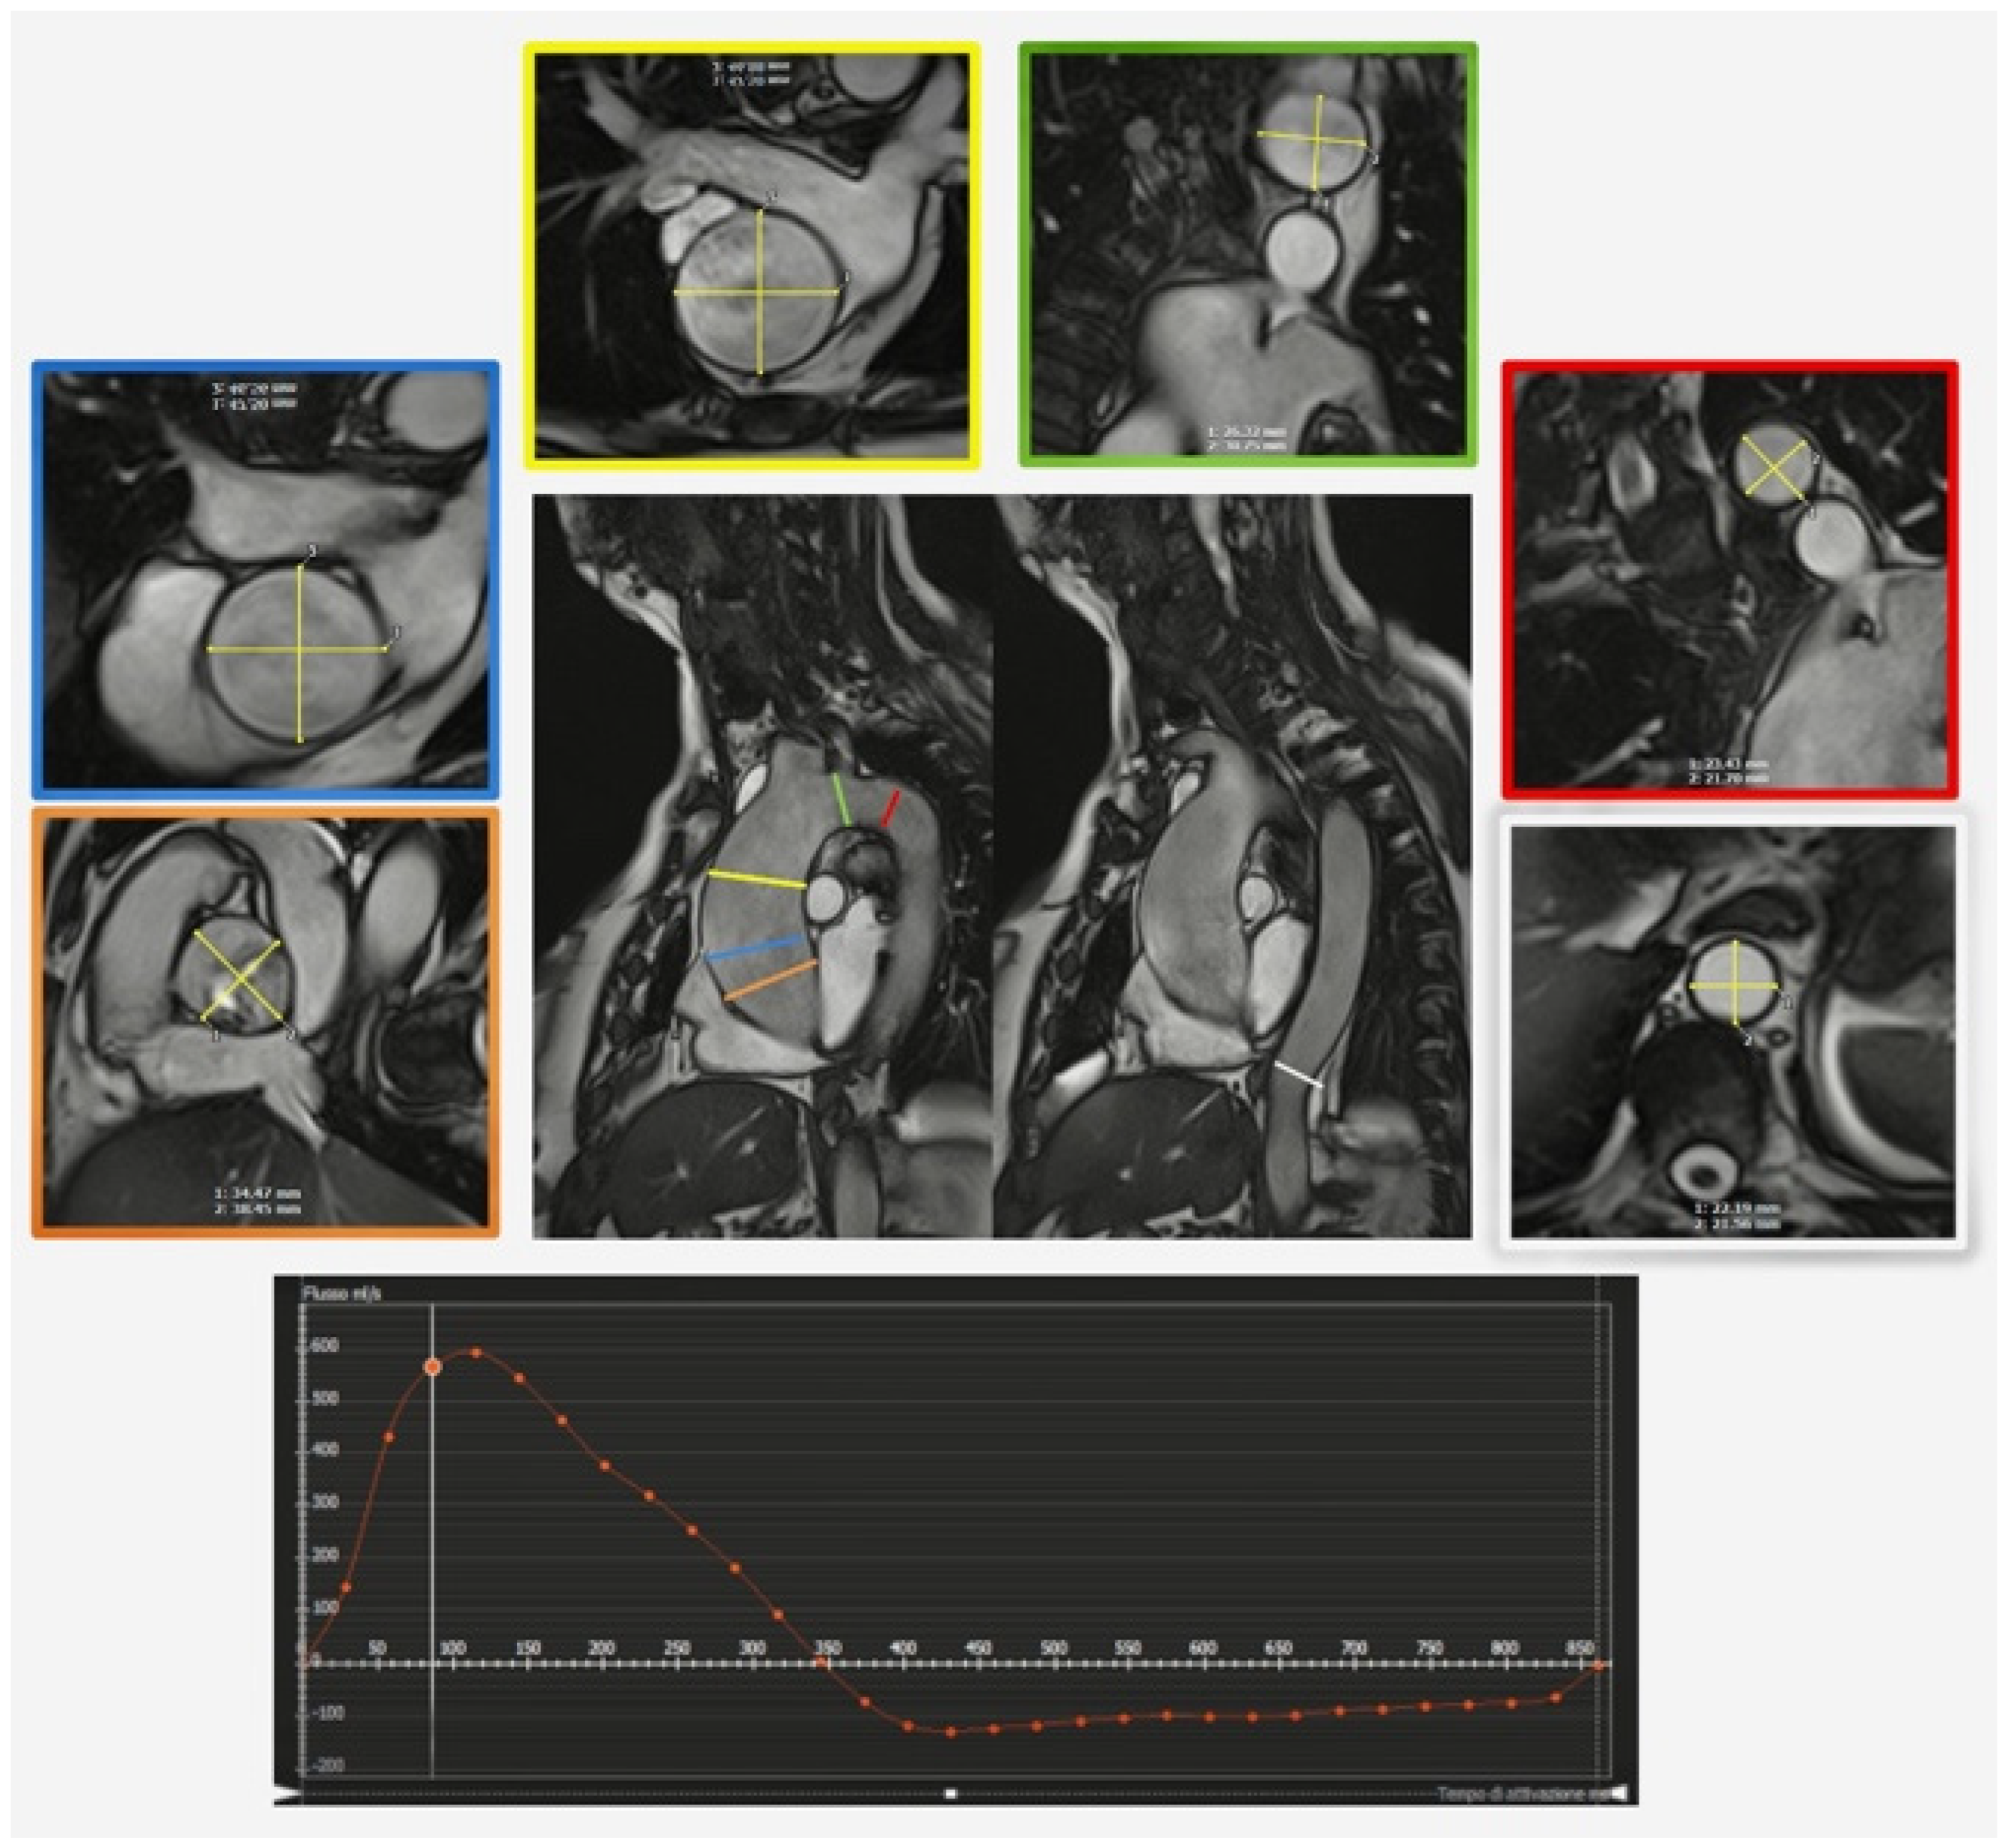

1.2. Magnetic Resonance

- Xu, J.; Yang, W.; Zhao, S.; Lu, M. State-of-the-art myocardial strain by CMR feature tracking: Clinical applications and future perspectives. Eur. Radiol. 2022, 32, 5424–5435. [Google Scholar] [CrossRef] [PubMed]

- Quinaglia, T.; Jerosch-Herold, M.; Coelho-Filho, O.R. State-of-the-Art Quantitative Assessment of Myocardial Ischemia by Stress Perfusion Cardiac Magnetic Resonance. Magn. Reson. Imaging Clin. N. Am. 2019, 27, 491–505. [Google Scholar] [CrossRef] [PubMed]

- Dyverfeldt, P.; Bissell, M.; Barker, A.J.; Bolger, A.F.; Carlhäll, C.-J.; Ebbers, T.; Francios, C.J.; Frydrychowicz, A.; Geiger, J.; Giese, D.; et al. 4D flow cardiovascular magnetic resonance consensus statement. J. Cardiovasc. Magn. Reson. 2015, 17, 72. [Google Scholar] [CrossRef] [PubMed]

- Francone, M.; Budde, R.P.J.; Bremerich, J.; Dacher, J.N.; Loewe, C.; Wolf, F.; Natale, L.; Pontone, G.; Redheuil, A.; Vliegenthart, R.; et al. CT and MR imaging prior to transcatheter aortic valve implantation: Standardisation of scanning protocols, measurements and reporting—A consensus document by the European Society of Cardiovascular Radiology (ESCR). Eur. Radiol. 2020, 30, 2627–2650. [Google Scholar] [CrossRef]